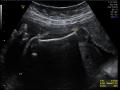

Tag: Ultrassonografia obstétrica

Gestação inicial

Ultrassonografia obs...